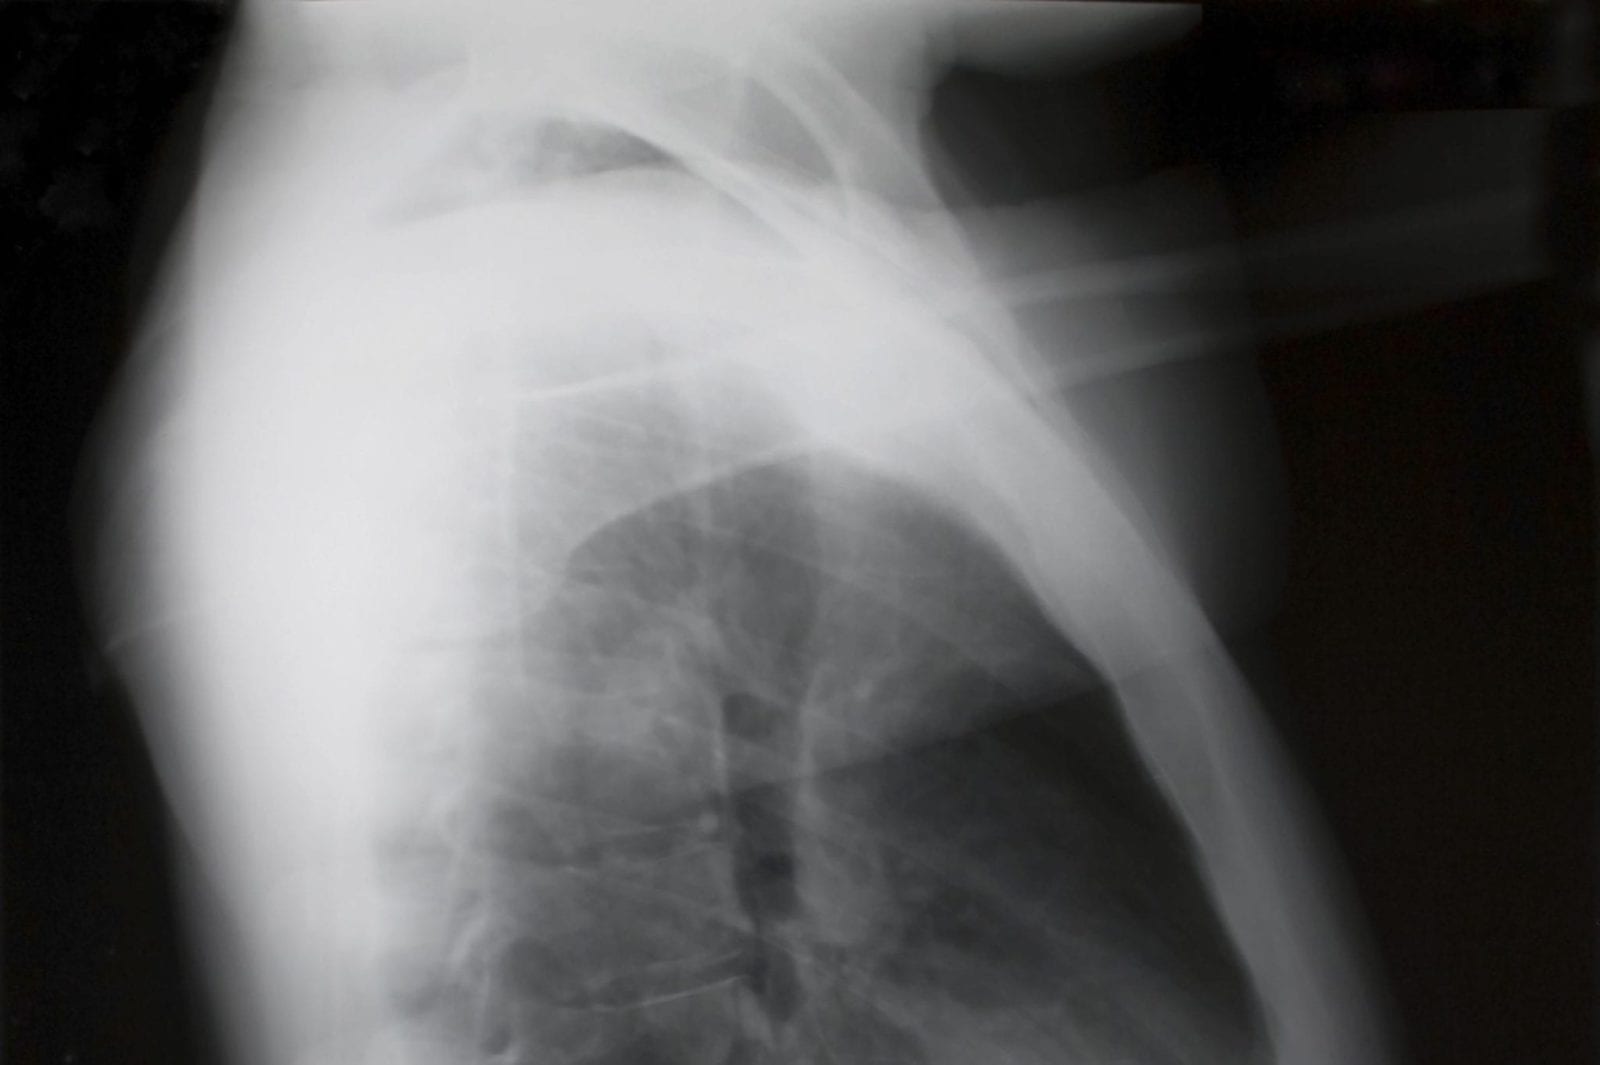

There are two types of mesothelioma; pleural and peritoneal. Pleural mesothelioma affects the lungs and chest, and closely mimics other conditions that affect the same area of the body. One of the most common complications of the disease, pleural effusion, involves a buildup of fluid in the chest cavity.